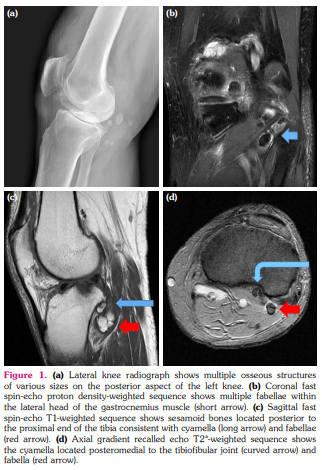

A 65-year-old male, formerly diagnosed with osteoarthritis, presented with a history of posterior knee pain lasting for three months. The patient had no previous history of significant trauma, except for a simple rotational injury that occurred while walking on an uneven surface. Physical examination revealed mild swelling, pain that increases with extension, snapping elicited upon extending the knee, localized tenderness, and warmth at the posterolateral aspect of the left knee. Plain radiographs demonstrated multiple osseous structures of various sizes. Magnetic resonance imaging revealed degenerative changes together with rice bodies in suprapatellar bursae and tendon sheaths of the medial gastrocnemius muscle and multiple osseous and fibrocartilaginous lesions located in the lateral gastrocnemius muscle and popliteus muscle, which were considered as multiple fabellae and cyamella, respectively (Figure 1).

gure 1). Conservative treatments including antiinflammatory medications, knee brace, avoiding excessive weight bearing, and physical therapy were applied. At the follow-up one month later, it was observed that the patient's complaints improved.